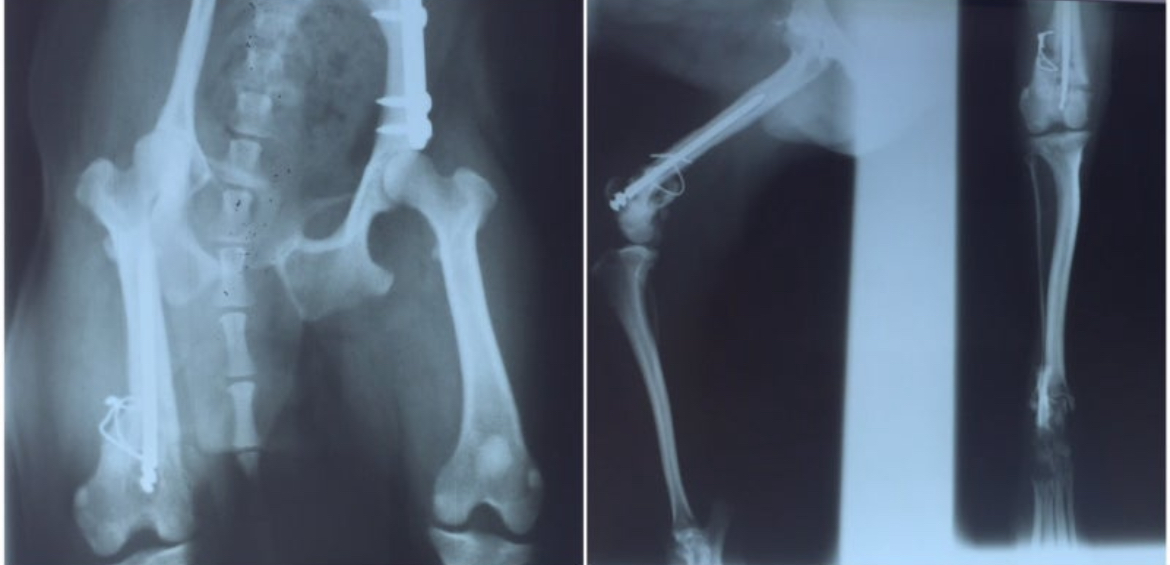

엑스레이 속 뼈는 얼기설기 이어져 있었다.

철사는 살을 찔렀고,

굳은 피가 근육과 엉켜 있었다.

수의사는 중얼거렸다.

“시대가 어떤 시댄데 이런 수술을…”

또랑이 뒷다리 둘다 교통사고(?) 후 골절 상태, 시골 병원에서 대충 얼기설기 철사로 묶어놓은 모습